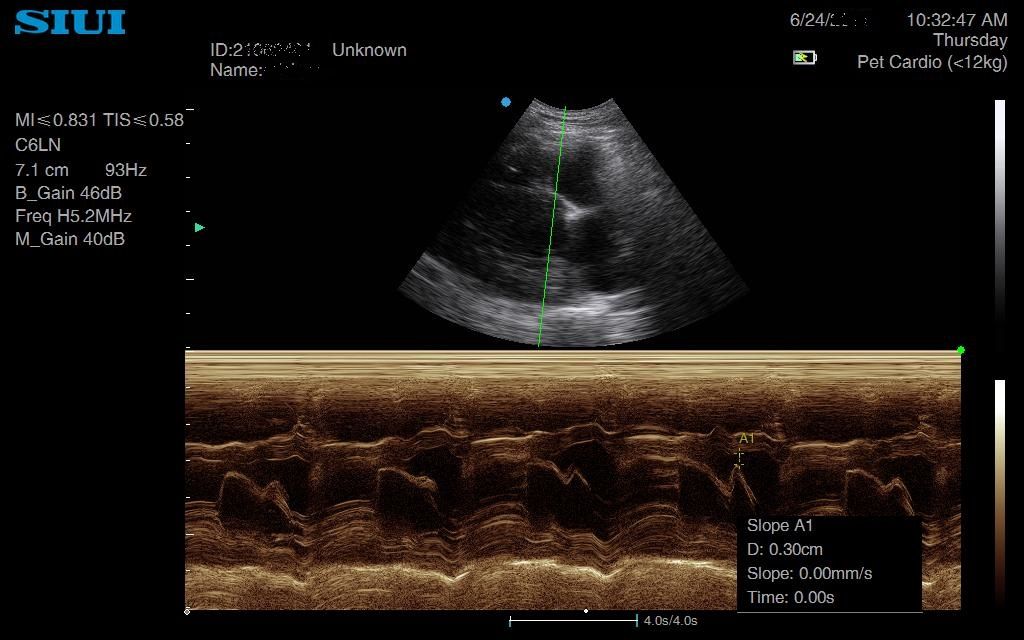

SIUI Apogee 1000V Review

This machine is brilliant. For the cost on paper – £6960 for the basic machine, including a microconvex probe the image quality is outstanding.

On top of this, the Colour Doppler is better than any other machine I have tried in this price range – the computing power can maintain a great frame rate while Doppler is on – meaning the image on the screen is real-time and crisp.

I used this machine for a couple of months on my peripatetic travels and am convinced I picked up on subtle changes I wouldn’t have seen with other machines.

Images